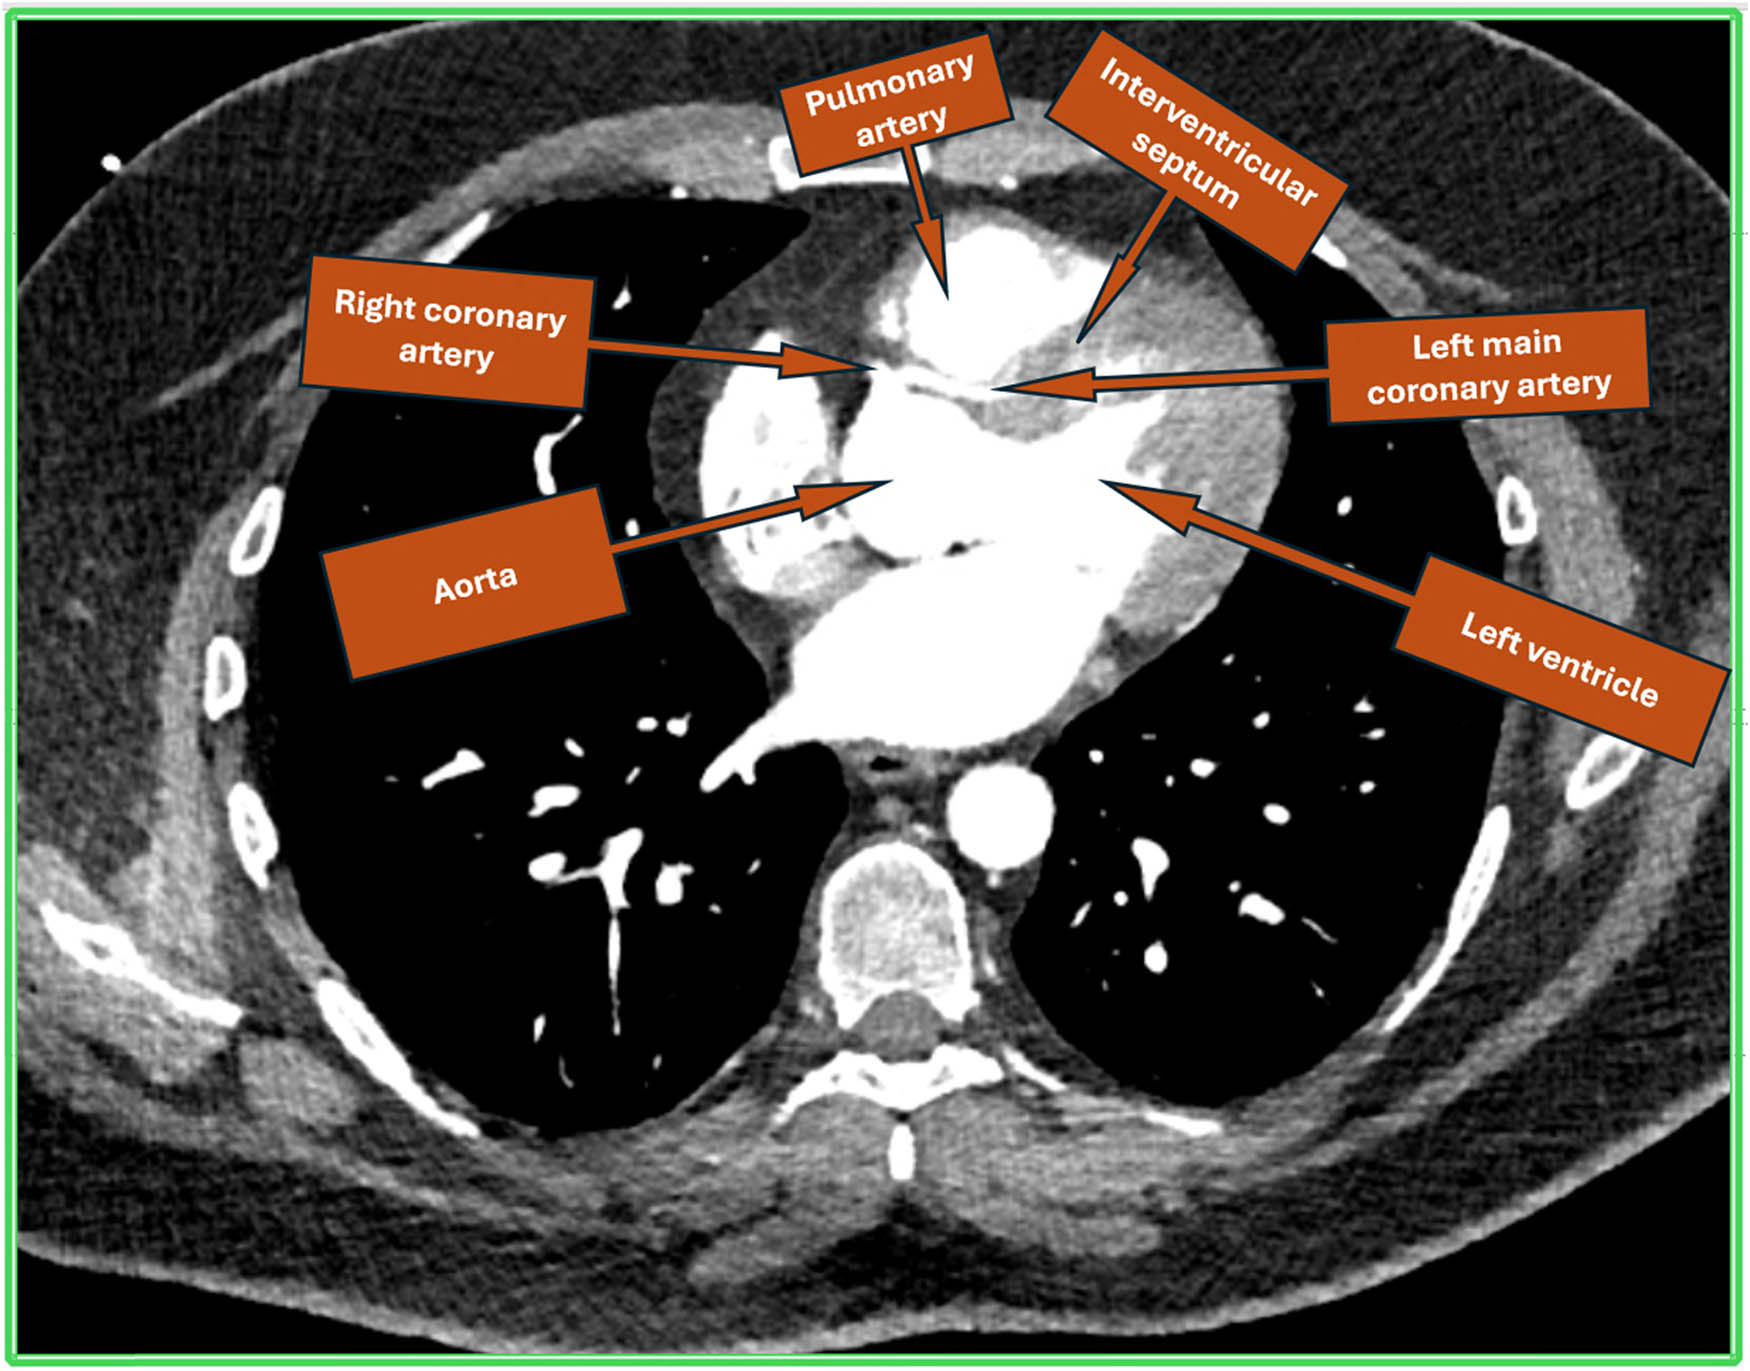

A 33-year-old male with a history of high BMI and smoking presented to the Rapid Access Chest Pain Clinic with exertional breathlessness and retrosternal chest tightness for the past 1 year. He reported a sharp decline in his exercise tolerance with recent difficulty when walking as little as 300 yards. One year earlier, he was able to exercise at high intensity in the gym. His workup included coronary computed tomographic angiography (CCTA) which demonstrated a common origin for the left and right coronary systems, via the right ostium of Valsalva (Figure 1). The left main stem (LMS), after taking off anomalously from the right coronary cusp, adopted an inter-arterial course between the main pulmonary trunk and aorta (Figure 2), progressing as a long intramural course through the aortic wall, before opening out into the aortic lumen. Throughout its path, the vessel exhibited mild, diffuse stenosis, likely due a combination of the slit-like ostial opening and dynamic compression between the aorta and pulmonary artery (PA). In comparison, the right coronary artery appeared to be dominant and of a larger calibre. No significant atheroma or stenosis could be visualised in either the main coronary system or in any important side branches.

Cardiac computed tomogram showing single coronary origin from right coronary cusp and LCA having inter-arterial course between aorta and PA followed by course in the interventricular septum.